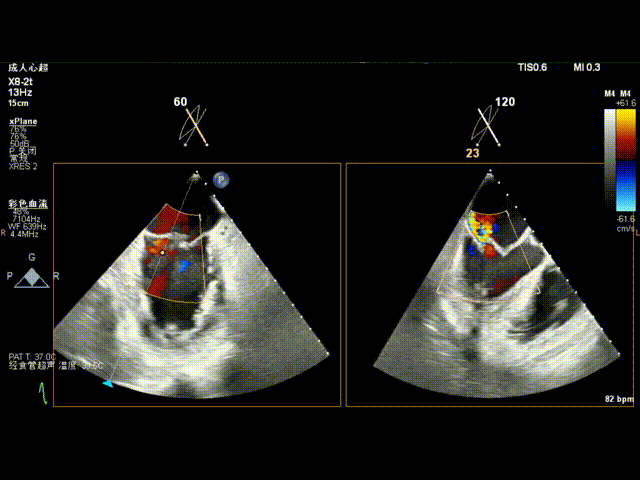

术前食道超声示: 二尖瓣重度反流,1区脱垂并累及外交界。

术前食道超声-2D血流

术前食道超声-3D

术前食道超声3D血流